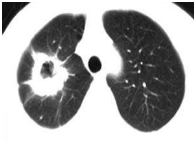

一名65岁女性因右胸痛和劳累性呼吸困难而去医院就诊。 胸部X线摄影显示右肺通透性降低。 计算机断层扫描